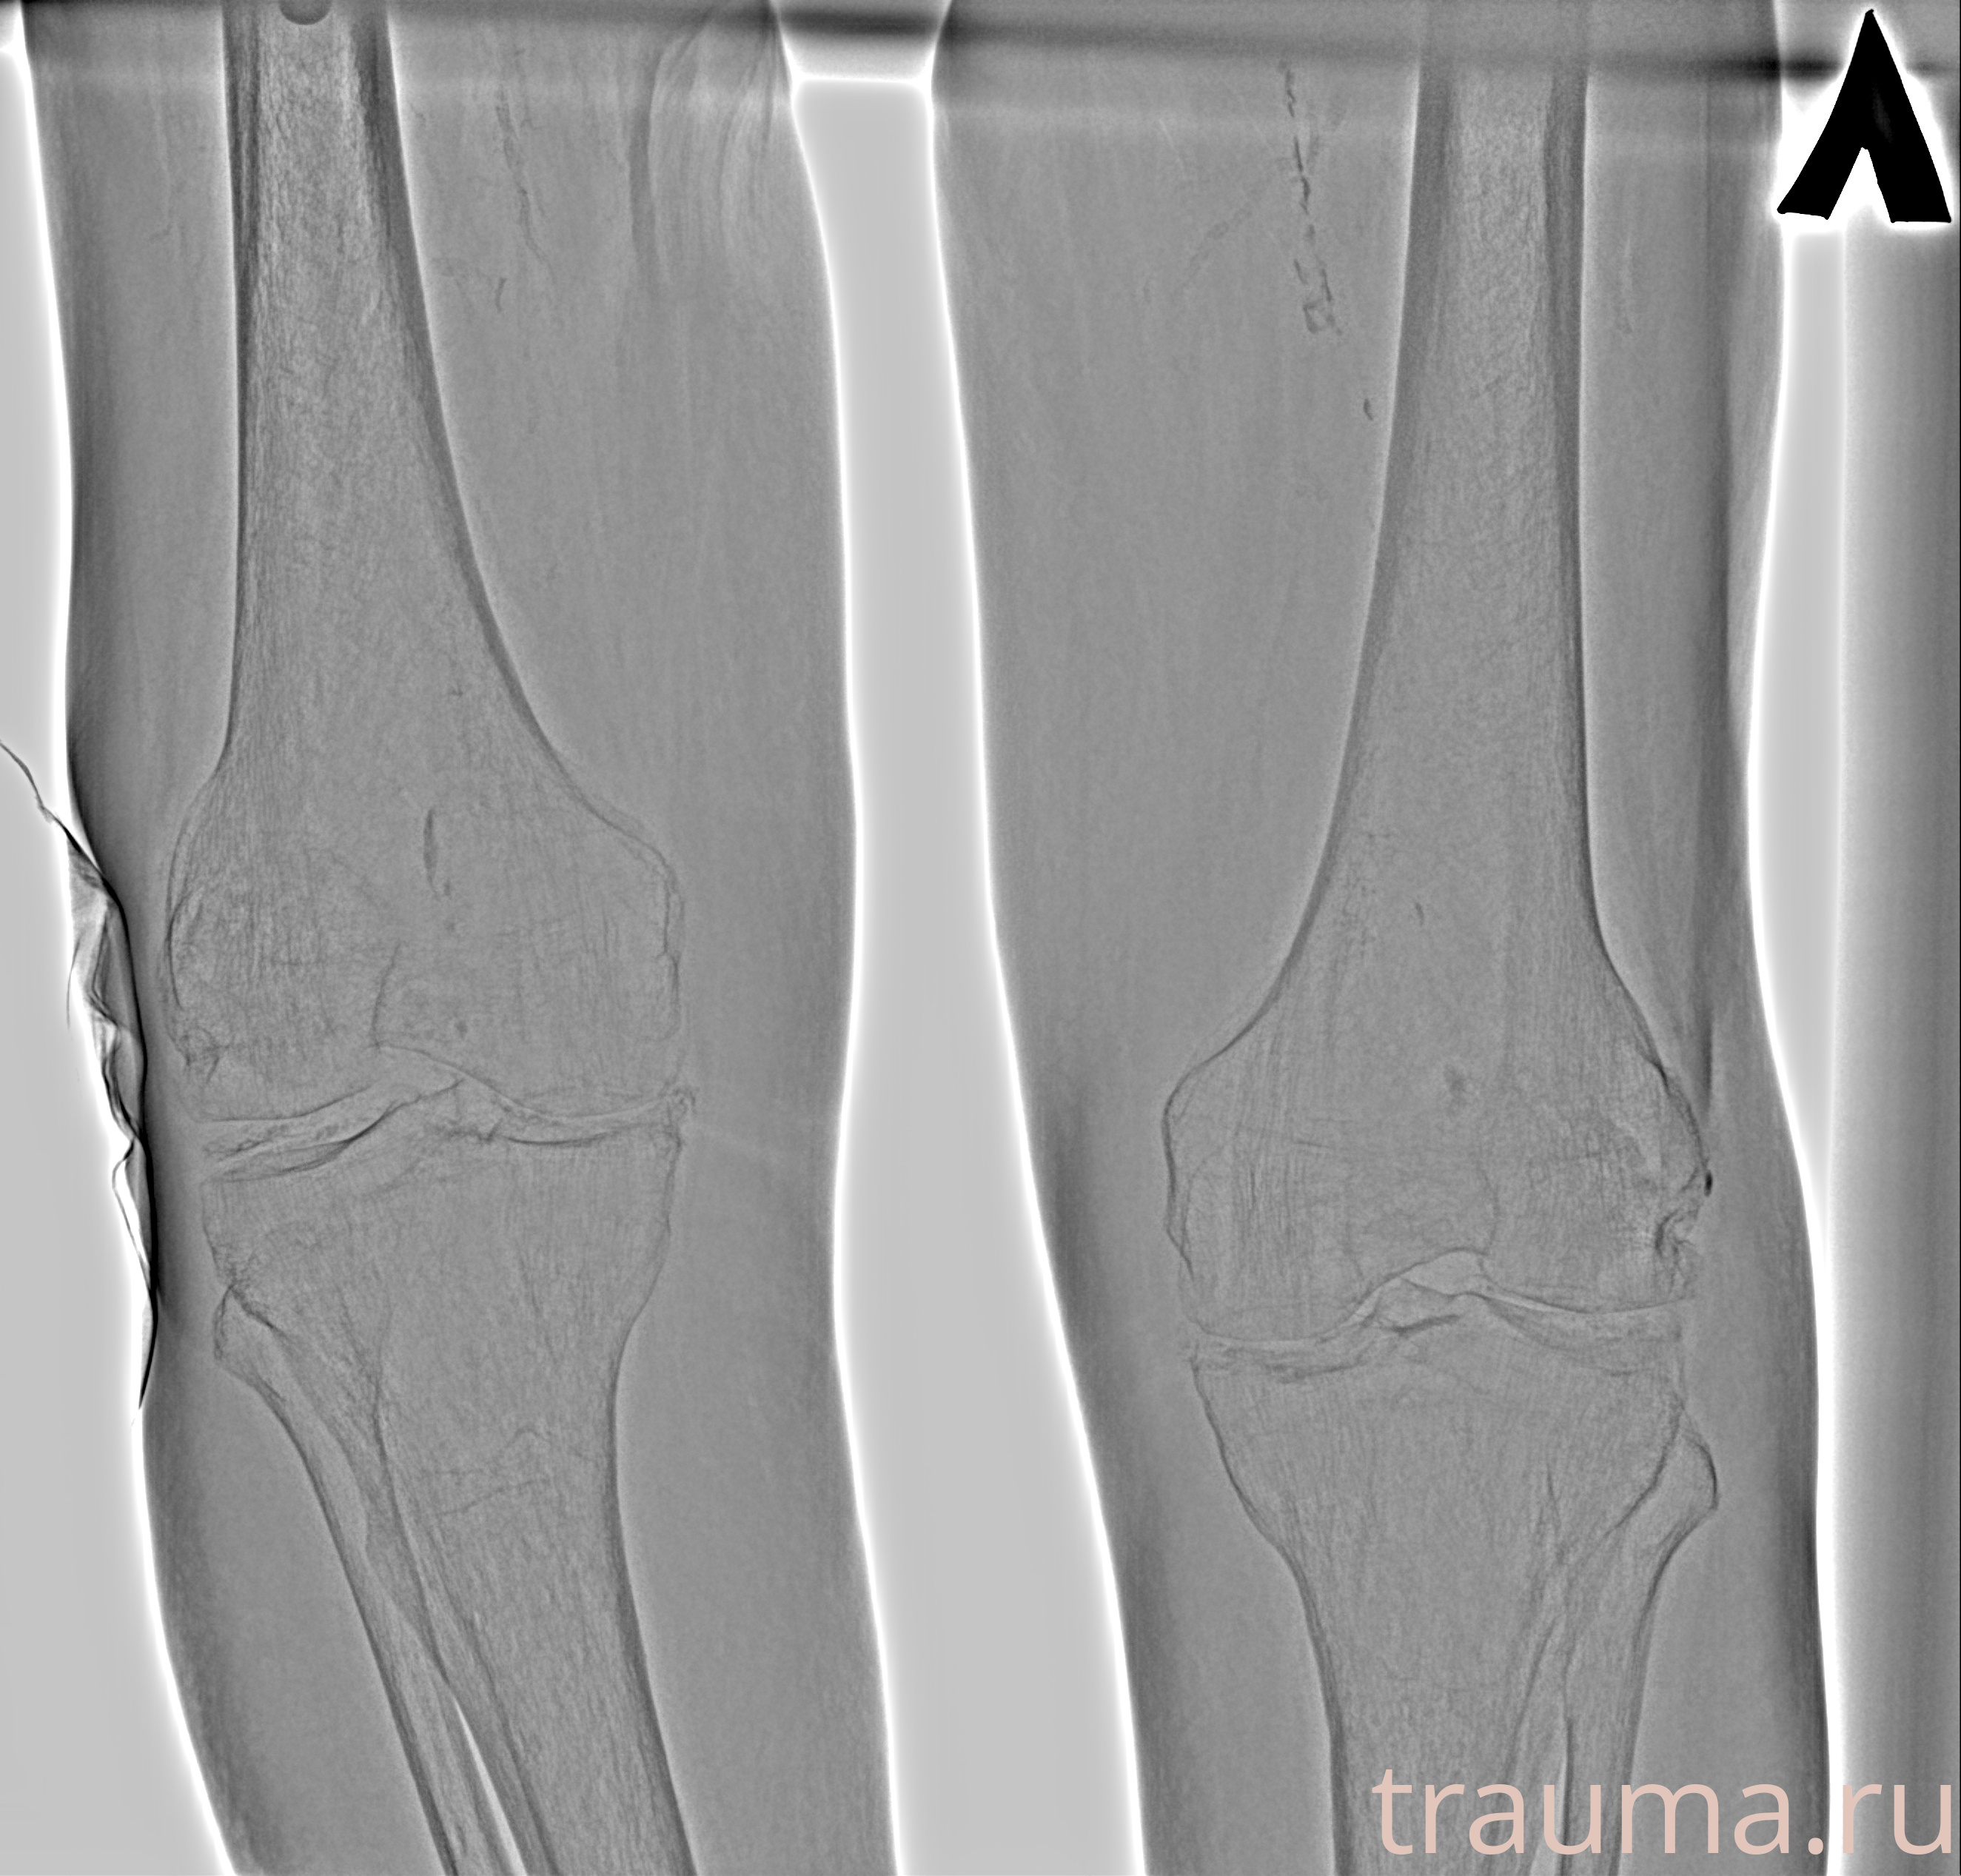

Рентген на дому: по вашему адресу приезжает врач-рентгенолог, травматолог-ортопед с мобильным рентгеновским аппаратом, проводит диагностику травмы или заболевания, делает необходимые рентгенограммы, дает рекомендации по дальнейшему лечению. Получить качественные снимки в домашних условиях возможно благодаря уникальной методике, разработанной МосРентген Центром для института  Склифосовского